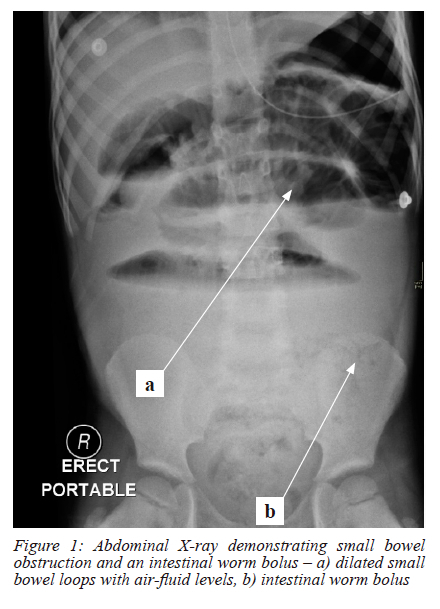

An abdominal X-ray demonstrated features of small bowel obstruction with a worm bolus visible within the small bowel (Figure 1). Arterial blood gas analysis revealed a compensated metabolic acidosis (pH 7.37, bicarbonate (HCO3) 14.8 mmol/l, base excess - 7.8 mmol/l, lactate 1.2 mmol/l and pCO2 3.3 Kpa) (normal ranges pH 7.35 -7.45, HCO3 22 - 26 mmol/l, base excess -2 - +2 mmol/l, lactate < 2 mmol/l and pCO2 4.7 - 6.0 Kpa respectively). Blood analysis showed a raised white cell count at 20.12 x 109/L (normal values 6.00 - 16.00 x 109/L). Of note, the eosinophil count was normal at 0 x109/l (normal values 0.0 - 0.5 x109/l) and haemoglobin was slightly elevated for his age at 15.4 g/dl (normal values 9.5 - 14 g/dL).

Diagnostic images for small bowel volvulus include plain abdominal X-rays that may identify small bowel obstruction and an abdominal contrasted tomography (CT) scan. An abdominal CT scan may demonstrate a characteristic whirlpool sign, however the accuracy to identify small bowel volvulus can be as low as 45%.8 Intestinal ascaris can sometimes be identified on plain abdominal X-rays. A large cluster of worms can be seen, highlighted by intestinal gas, with an irregular border between the worm mass and the surrounding gas shadows. Individual worms may appear as linear or bubble-shaped radiolucency.9